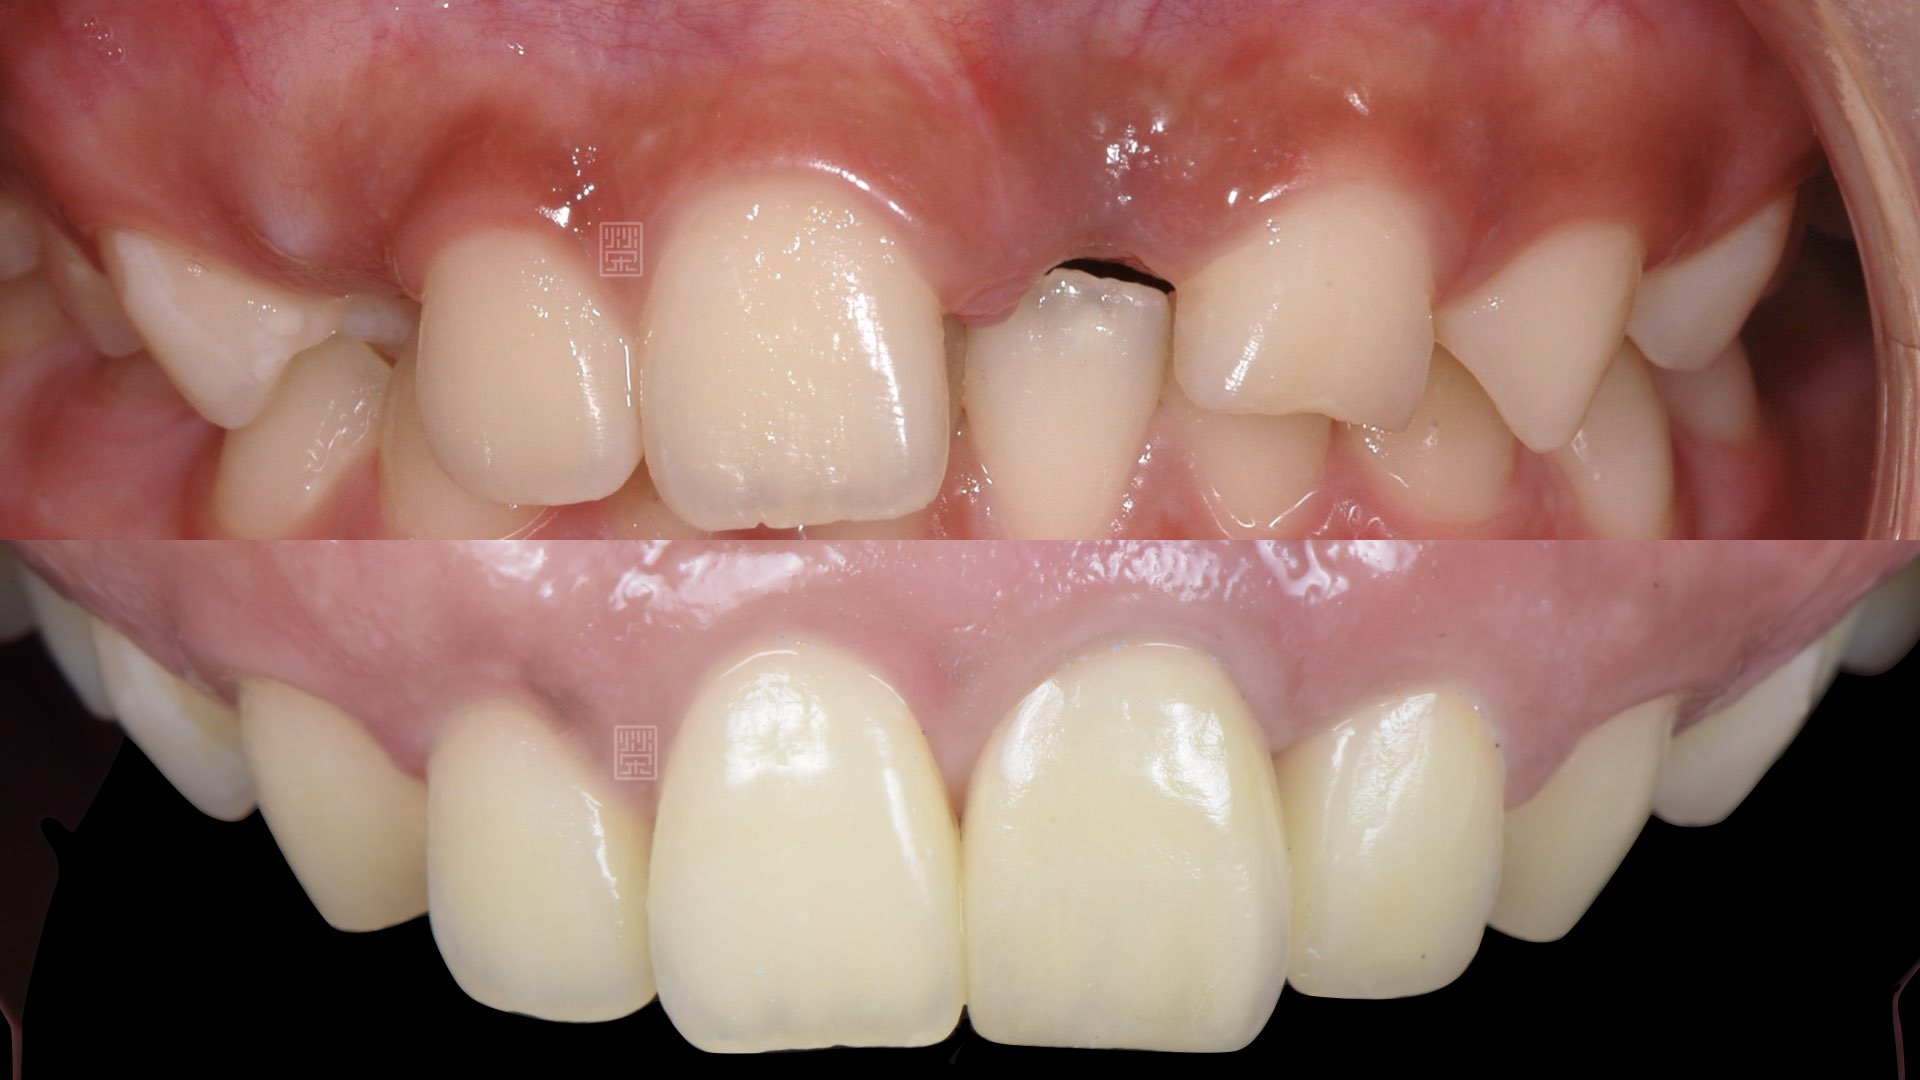

治療十二年後馬利蘭牙橋

牙齦軟組織重建

植牙臨時假牙